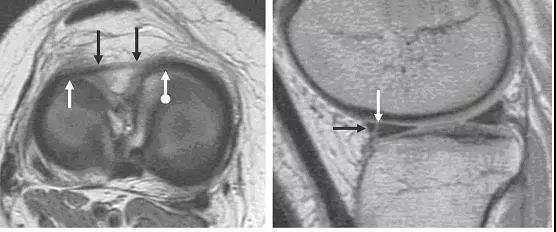

图 5 正常后交叉韧带和半月板股骨前后韧带

左图:经过后交叉韧带的矢状面,显示连续均质低信号的后交叉韧带(黑色箭头),其前方是半月板股骨前韧带(Humphry 韧带,白色箭头)。右图:冠状位片显示半月板股骨后韧带(Wrisberg 韧带,黑色短箭头不带圆点)从外侧半月板后角(黑色长直箭头)连接到股骨内侧髁外面。同时可见腘腓韧带(白色箭头)从腓骨头到腘肌腱(黑色短圆箭头),P 为后交叉韧带。